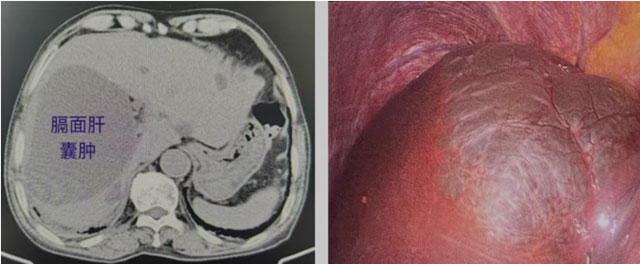

他的膈面肝囊肿

长在膈面的肝囊肿因位置特殊,是肝囊肿治疗中的“硬骨头”,传统B超穿刺硬化、腹腔镜开窗引流等方式,都难逃高复发困境。因膈面肝囊肿紧邻膈肌,常规开窗术后,膈肌会像塌下来的天花板一样贴合肝脏表面,刚打开的囊腔极易再次封闭,这也是其复发率远高于普通肝囊肿的关键,不少患者因此反复手术。